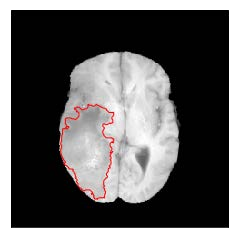

Machine learning has been widely adopted for medical image analysis in recent years given its promising performance in image segmentation and classification tasks. The success of machine learning, in particular supervised learning, depends on the availability of manually annotated datasets. For medical imaging applications, such annotated datasets are not easy to acquire, it takes a substantial amount of time and resource to curate an annotated medical image set. In this paper, we propose an efficient annotation framework for brain MR images that can suggest informative sample images for human experts to annotate. We evaluate the framework on two different brain image analysis tasks, namely brain tumour segmentation and whole brain segmentation. Experiments show that for brain tumour segmentation task on the BraTS 2019 dataset, training a segmentation model with only 7% suggestively annotated image samples can achieve a performance comparable to that of training on the full dataset. For whole brain segmentation on the MALC dataset, training with 42% suggestively annotated image samples can achieve a comparable performance to training on the full dataset. The proposed framework demonstrates a promising way to save manual annotation cost and improve data efficiency in medical imaging applications.

翻译:近年来,由于在图像分割和分类任务方面表现良好,医学图像分析广泛采用了机器学习。机器学习的成功,特别是监督学习的成功,取决于手动附加说明数据集的可用性。对于医疗成像应用来说,这种附加说明数据集不容易获得,需要大量的时间和资源来翻译附加说明的医学成像集。在本文件中,我们建议为大脑MR图像建立一个高效的注释框架,为人类专家提供信息性样图像,供人类专家作说明。我们评估了两种不同的大脑图像分析任务的框架,即脑肿瘤分割和整个大脑分割。实验显示,对于BRATS 2019数据集的脑肿瘤分割任务,培训一个只有7%的附加说明图像样本的分解模型,其性能与全数据集培训的性能相当。对于MALC数据集的整个大脑分割,用42%的附加说明性图像样本进行的培训,可以实现与全数据集培训的类似性能。拟议的框架展示了节省人工注解成本和提高医疗成像应用数据效率的有希望的方法。